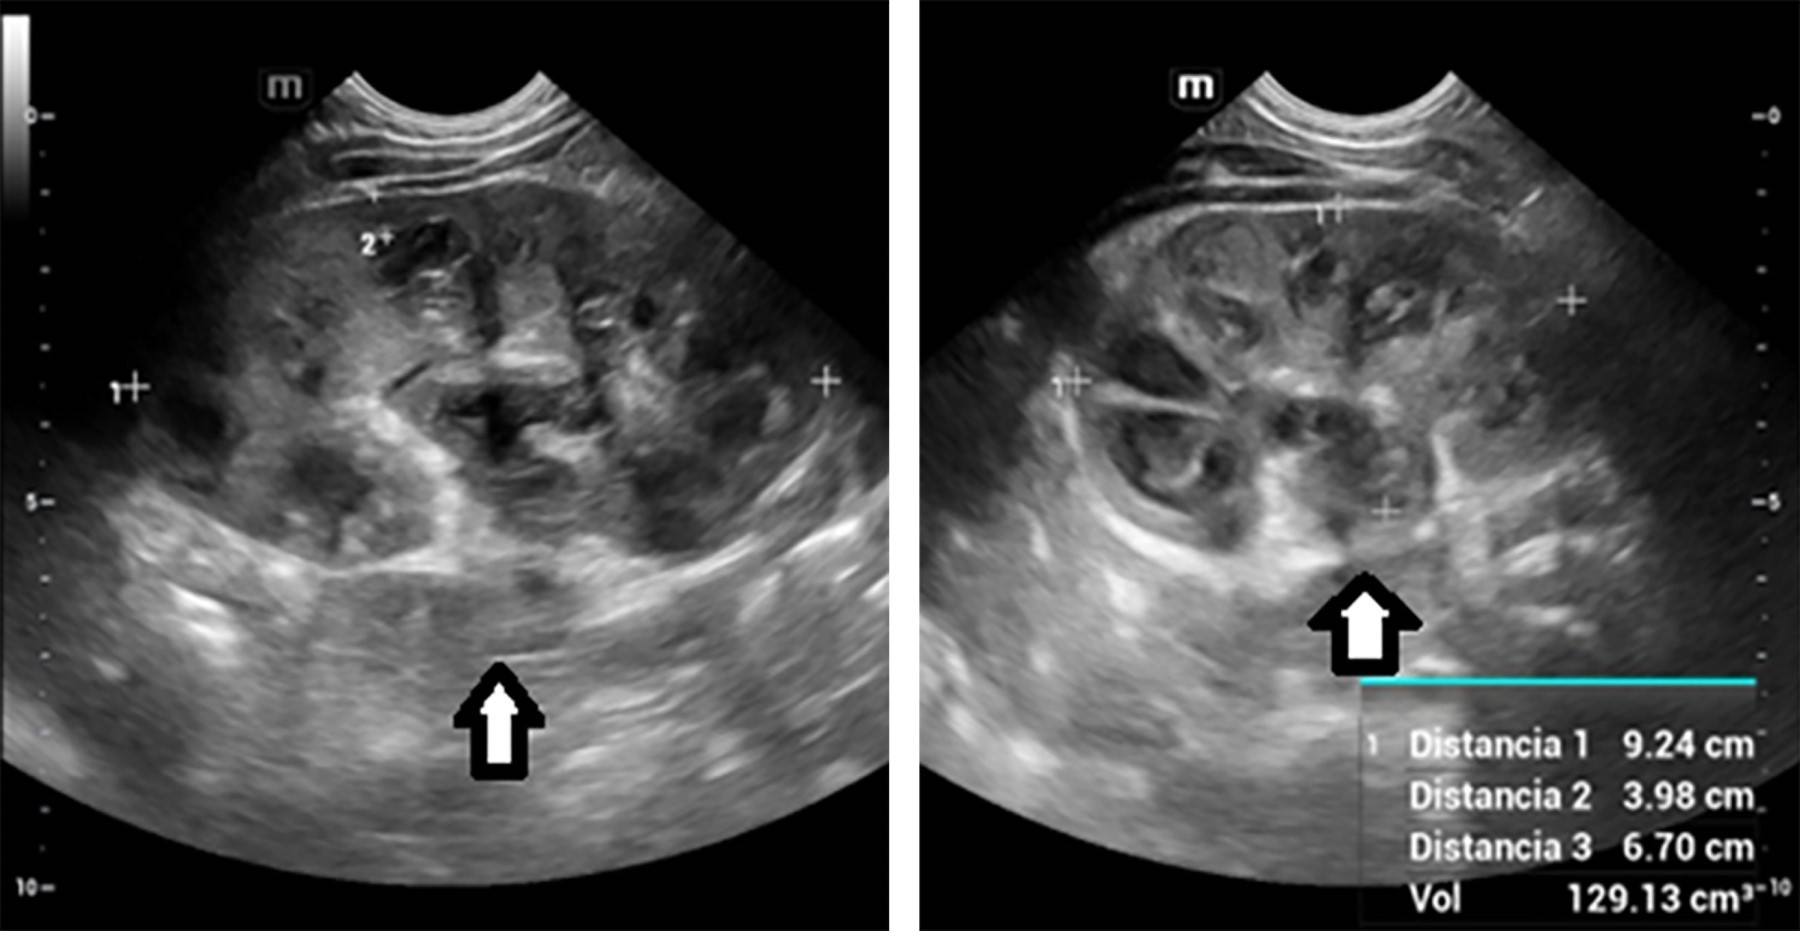

En los paraclínicos de ingreso presentaba anemia moderada, trombocitosis, leucocitosis a expensas de neutrófilos, pruebas de función renal y hepática normales, proteína C reactiva elevada y uroanálisis sugestivo de proceso infeccioso (Tabla 1). En la ecografía de vías urinarias se evidenció aumento del tamaño del riñón izquierdo con dilatación de la pelvis renal y de los cálices centrales y periféricos con material ecogénico en su interior (Figura 1). Por sospecha de absceso renal se inicia antibiótico de amplio espectro (ceftriaxona). El urocultivo de ingreso no mostró crecimiento bacteriano a las 48 horas de incubación. Por el hallazgo por ultrasonido se realiza tomografía donde se identifica dilatación de la pelvis renal izquierda de 25 mm de diámetro por presencia de cálculo obstructivo a nivel de la unión pieloureteral. Completa 14 días de tratamiento antibiótico con resolución de la fiebre y el urocultivo al finalizar la terapia sin crecimiento bacteriano. Por los antecedentes se decide mantener profilaxis antibiótica con cefalosporina de primera generación.

El diagnóstico por medio de ultrasonografía se basa en la identificación de una masa ecogénica móvil o como una lesión hipoecoica con un borde de áreas ecogénicas periféricas.5,6 En tomografía se observan lesiones isodensas, ovales y bien definidas, las cuales pueden confundirse con datos de urolitiasis.6 El estudio microbiológico en orina es difícil de interpretar, ya que la aparición de Candida en una muestra puede ser debido a contaminación, por ello, es fundamental realizar correlación clínica y de imagen para esclarecer el diagnóstico.7

Figura 1